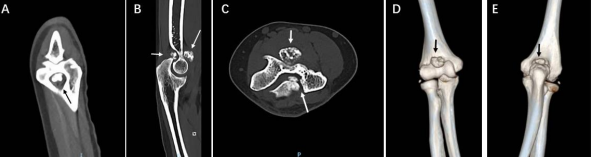

However, on clinical examination, she has laxity lateral elbow joint with collateral ligament stress test positive and chair pushing up test+ and elbow pivert shift test + indicating LUCL chronic instability. Two years after index surgery, she has complained the elbow pain and progressively worsening on ROM; joint with flex up to 90 degrees and extension blocking in 30 degrees to full extension (FFD 30 degrees). The lateral and the A-P radiographs of the elbow showed numerous chondral calcifications (Figure 5). CT scans showed osteochondral lesions at anterior and posterior parts of the elbow (Figure 6). Sagittal view of CT scans showed that posterior capitalum bony defect indicating previous intra articularly osteochondral injuries (traumatic OCD lesion) (Figure 7). Prior to second surgery, CT angiogram scans showed the humerus artery at least 10 mm anterior to anterior elbow osteochondral lesion, relatively safe for arthroscopically assisted surgery (Figure 8).

Figure 5. Two years after index surgery, she has elbow pain and progressively worsening on ROM of the elbow with flexion up to 90 degrees and extension blocking in 30 degrees to full extension (FFD 30 degrees). Radiographs showed osteochondral calcification in front of the coronoid process and olecranon fossa (arrows)

Figure 6: Two years after index surgery, CT scans showed anterior and posterior elbow osteochondral lesions (arrows).

Figure 7: Sagittal view of CT scans showed that posterior capitalum bony defect indicating previous intra articularly osteochondral injuries (traumatic OCD lesion)

Figure 8. Two years after index surgery, CT angiogram scans showed the humerus artery at least 10 mm anterior to anterior elbow osteochondral lesion (arrows in B and C), relatively safe to do arthroscopically surgery